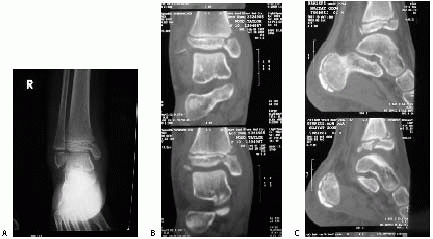

![]() |

FIGURE 26-48 Preoperative (A,B) and postoperative (C,D) anterior posterior and lateral views of an adolescent pilon fracture.

patient, these injuries can be associated with severe soft tissue

intervention for 5 to 15 days (Fig. 26-49).51